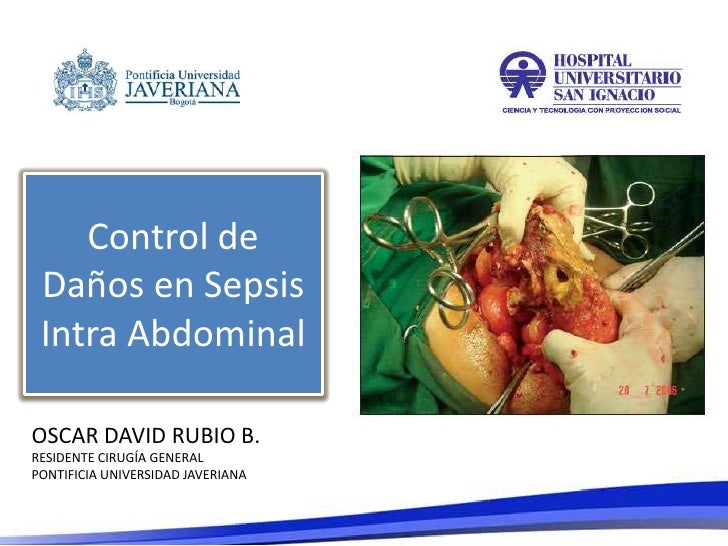

Sepsis intra abdominal

Sepsis intra abdominal

Sepsis intra abdominal

Sepsis intra abdominal